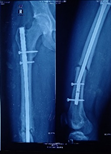

Case-II

26 years, male;

Re-fracture shaft of femur with bending plate and quiescent type infection. H/0-fall (Figure 5-10)

Figure 5 Post-operative x-ray after Plate Osteo-synthesis.

Figure 6 X-ray after re-fracture due to fall.

Figure 7 Post-operative x-ray after mount ilizarov frame kept plate in situ.

Figure 8 X-ray after removal of plate and consolidation.

Figure 9 Post-operative pictures with ilizarov frame.

Figure 10 Pictures after full recovery from fracture after one (1) year and four (4) months.

Re-fractures are another complication by further trauma where implant failure (Broken, Bending, Loosening) in the region of improper callus formation. The incidence of re-fracture is 6.5 to 14.2%.10 Approximately 5 - 12% non-union occurs in all fracture and it is around 20% for diaphyseal fracture.11,12 On average 200 cases of long bone non-union occur per million populations, estimating of 150.000 cases in Europe each year.13–15